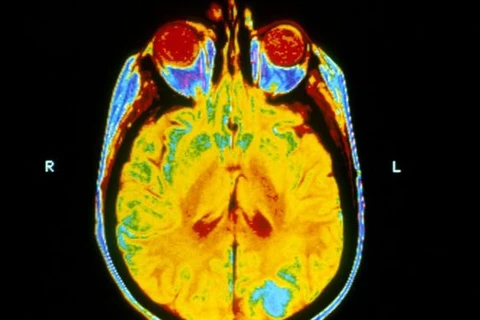

Ảnh minh họa. (Nguồn: News.yale.edu)

Ảnh minh họa. (Nguồn: News.yale.edu) Số liệu của Cơ quan Thống kê Anh (ONS) cho biết hầu hết bệnh nhân mắc những bệnh ung thư thường gặp như ung thư da, ung thư vú và ung thư tiền liệt tuyến tại Anh đều có thể sống thêm được 10 năm.

Tuy nhiên, điều may mắn này chỉ xảy ra đối với những bệnh nhân mắc chứng ung thư thông thường nói trên, còn đối với những chứng bệnh như ung thư tụy, phổi và não thì tỷ lệ sống thêm được 10 năm chỉ chiếm có 5,7%, 9,8% và 11,9% số bệnh nhân mắc phải.

Tuy nhiên, điều này chỉ có thể làm được khi bệnh nhân phát hiện được sớm còn những bệnh nhân ở vào giai đoạn cuối thì không có cơ hội kéo dài lâu đến vậy vì họ thường sẽ gặp phải những biến chứng di căn vào những bộ phận quan trọng như phổi, não./.